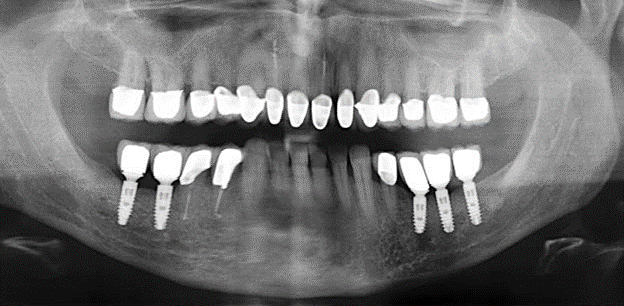

Fig. 3: Radiografia panoramica dopo dieci anni con impianti.

Il controllo decennale non ha rivelato alcuna indicazione dell'avanzamento della perdita di attaccamento clinico o della perdita di sostanza ossea perimplantare (Fig. 3).